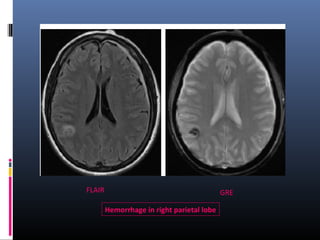

GREFLAIR

Hemorrhage in right parietal lobe